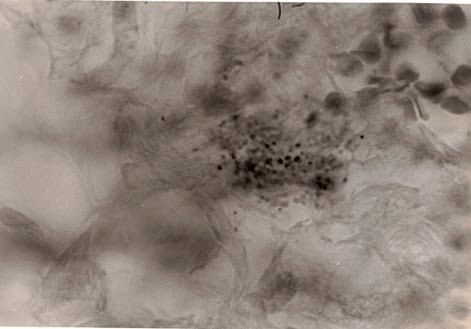

Figure 1. Tissue section of breast cancer showing numerous extracellular

coccoid forms in the tumor area.

The wrinkled large round forms at the upper right are red blood cells. Fite

(acid-fast) stain, magnification x1000, in oil.